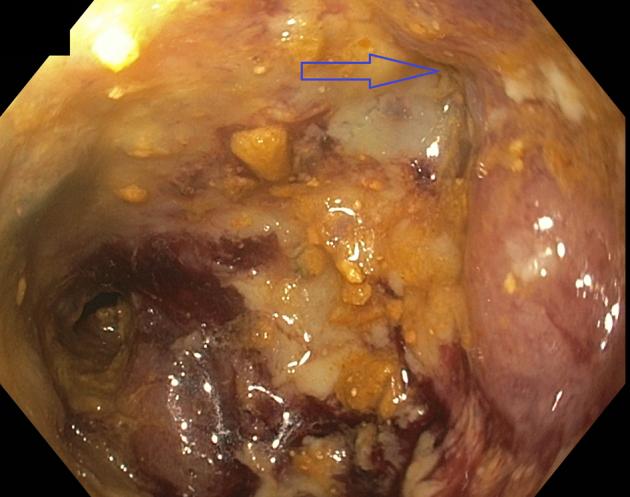

Colovaginal fistula (CVF) in cancer patients can cause significant morbidity. In addition to causing local symptoms and infections, the constant stool leakage contributes to a poor quality of life, psychological distress, and possible social isolation. Patients with CVFs often have advanced disease, poor nutrition, and complex anatomy, making them poor candidates for major surgical interventions. Advancement in endoscopic tools has made endoscopic management possible. Endoscopic management is less invasive, is associated with prompt recovery, and can significantly improve the quality of life of patients and possibly allow them to resume systemic therapy.

In this video case series, 3 cases of CVF patients treated endoscopically are presented to demonstrate the use of the currently available tools and techniques. The strategy used for the closure of the 3 CVFs was dependent on the size and etiology of the fistulas.

These cases demonstrate the use of the cap to perform vaginal endoscopy; the use of the over-the-scope clips, covered stents, and endoscopic suturing; and how they can facilitate the closure of fistulas in patients who are poor surgical candidates.